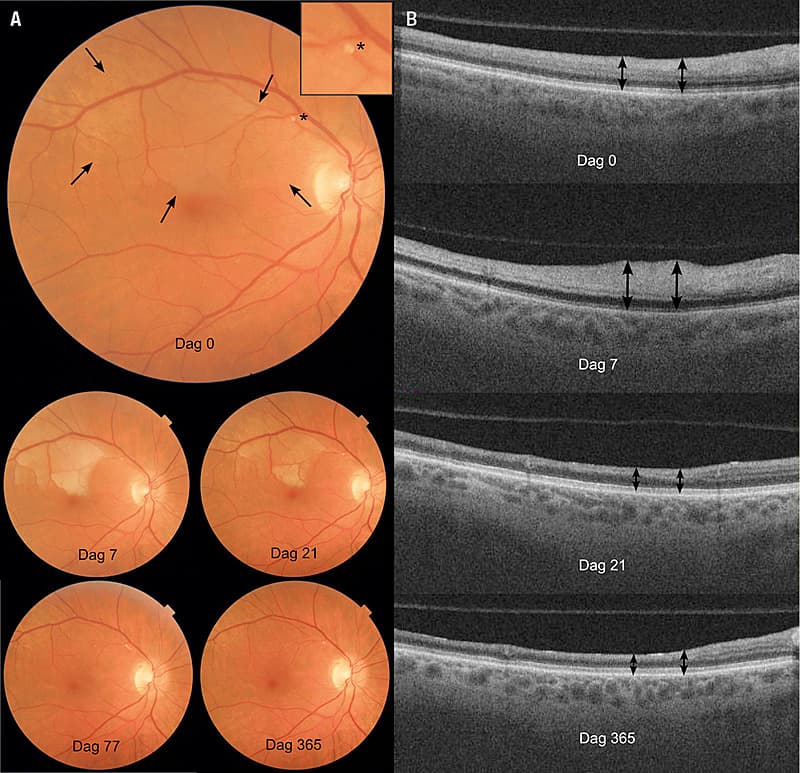

På billedet ses et fundusfoto af højre øje (A) og optisk kohærenstomografi (OCT) (B) i højde med plaquen.

* indikerer okklusionen. Sorte pile viser iskæmisk område. Dobbeltpil på OCT viser nethindetykkelsen i højde med plaquen.